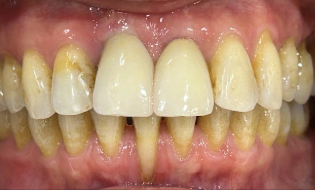

After

Figures 10 & 11

Figures 10 and 11 are a couple more cases which show our single incisor restorations which are notoriously difficult to get aesthetically right.